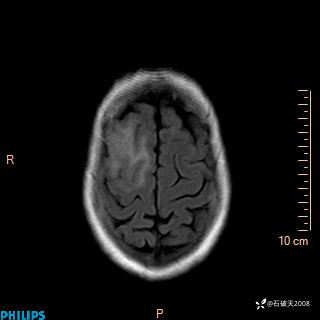

2020.11.14MR

T1